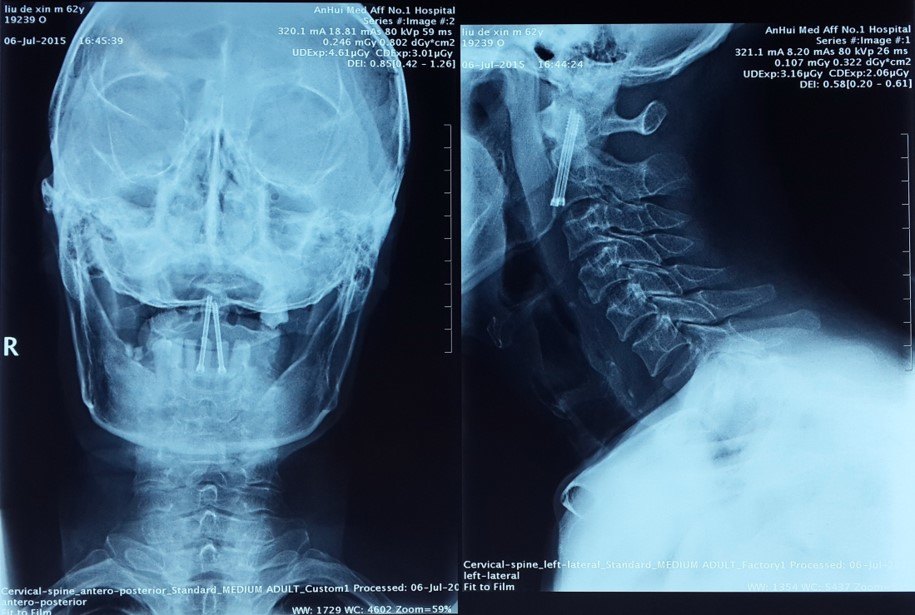

颈椎前路螺钉内固定治疗c2齿状突骨折(Ⅱ型)

颈椎核磁示:c2椎体齿状突基底部骨折

环枢关节ct 三维重建:枢椎齿状突基底部骨折